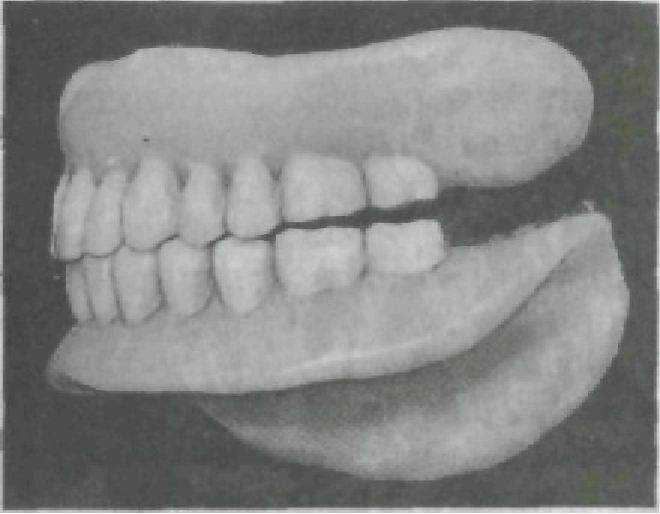

Фиксация нижней челюсти не в центральном соотношении, а в переднем, заднем или боковом (правом, левом). Наиболее частой ошибкой при определении центрального соотношения челюстей является выдвижение нижней челюсти вперед и фиксация ее в таком положении. При проверке конструкции будет прогнатическое соотношение зубных рядов, преимущественно бугорковое

смыкание боковых зубов, просвет между передними зубами, повышение прикуса на высоту бугорков (рис. 220).

Рис.220. Соотношение зубных рядов при фиксации нижней челюсти в сагиттальном положении.